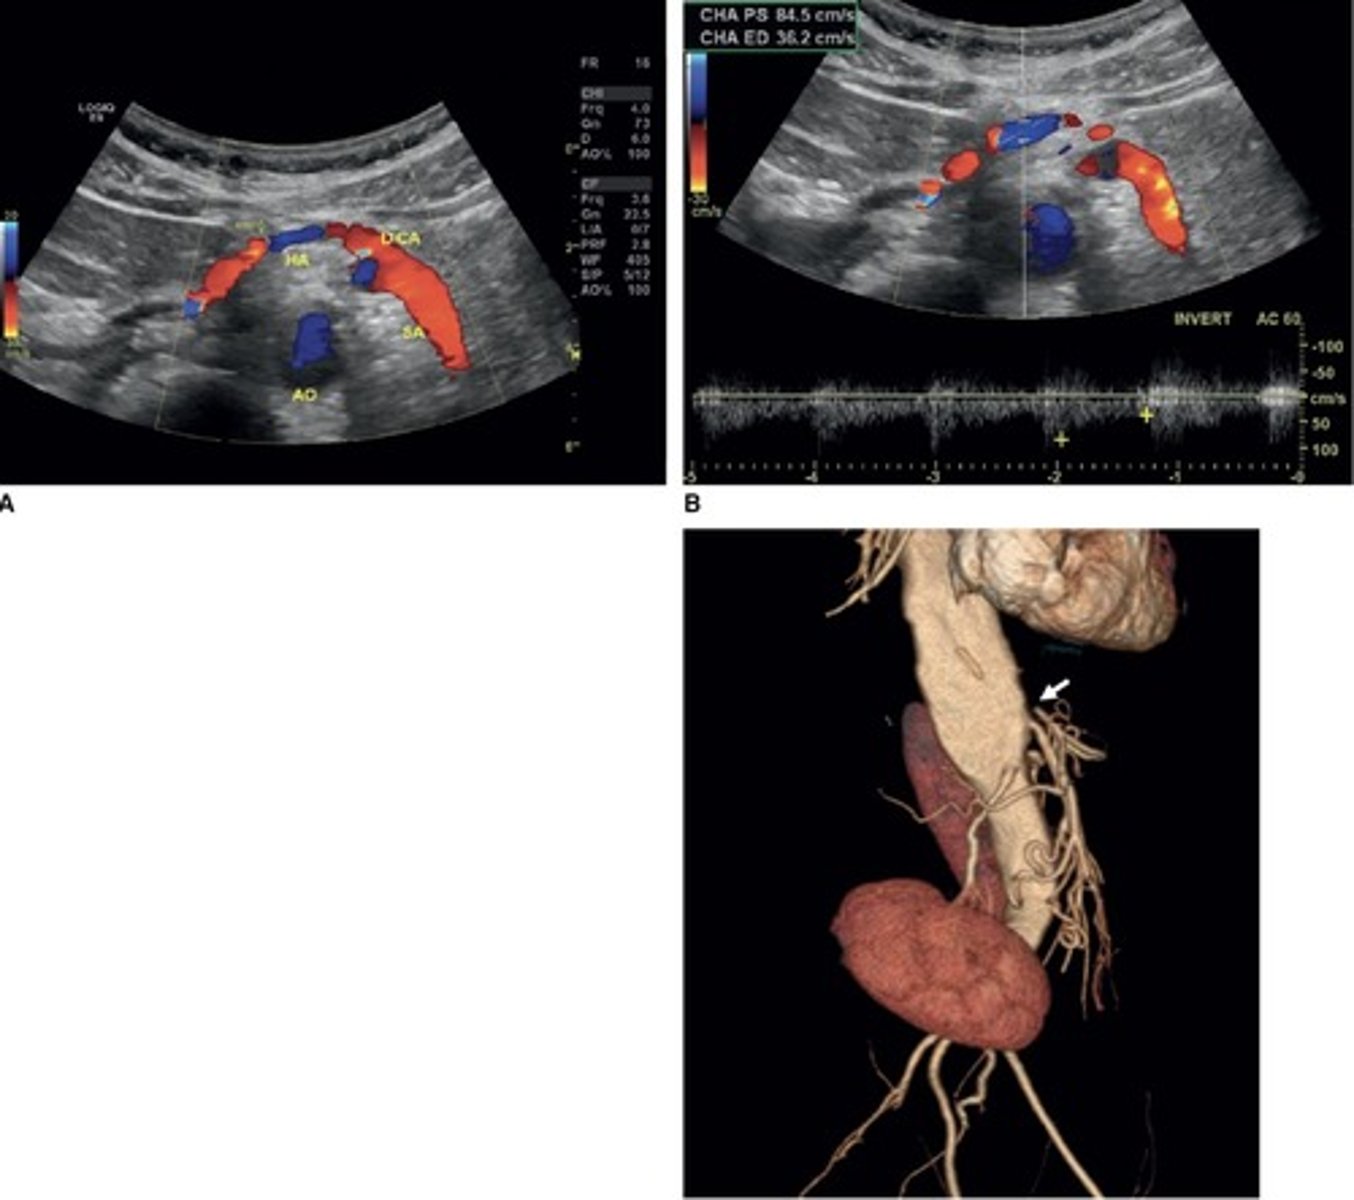

Hepatic Artery Retrograde Flow

Due to celiac artery occlusion

Blood flows towards splenic artery - RABT color pattern

Common Trunk Variant

Celiac and SMA come off common trunk